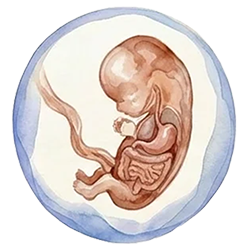

SMART NT brings together two powerful tools – high-resolution early ultrasound and advanced NIPT – in a planned way, so that structural and genetic problems linked to increased NT can be looked for much earlier and in more detail than with standard pathways. Instead of waiting until the traditional 20-week anomaly scan, SMART NT focuses on expert scans at around 10 and 12–13 weeks, with particular attention to the baby’s heart, brain, face, abdomen and skeleton. This allows many serious anomalies that are often associated with raised NT to be suspected or diagnosed several weeks earlier.